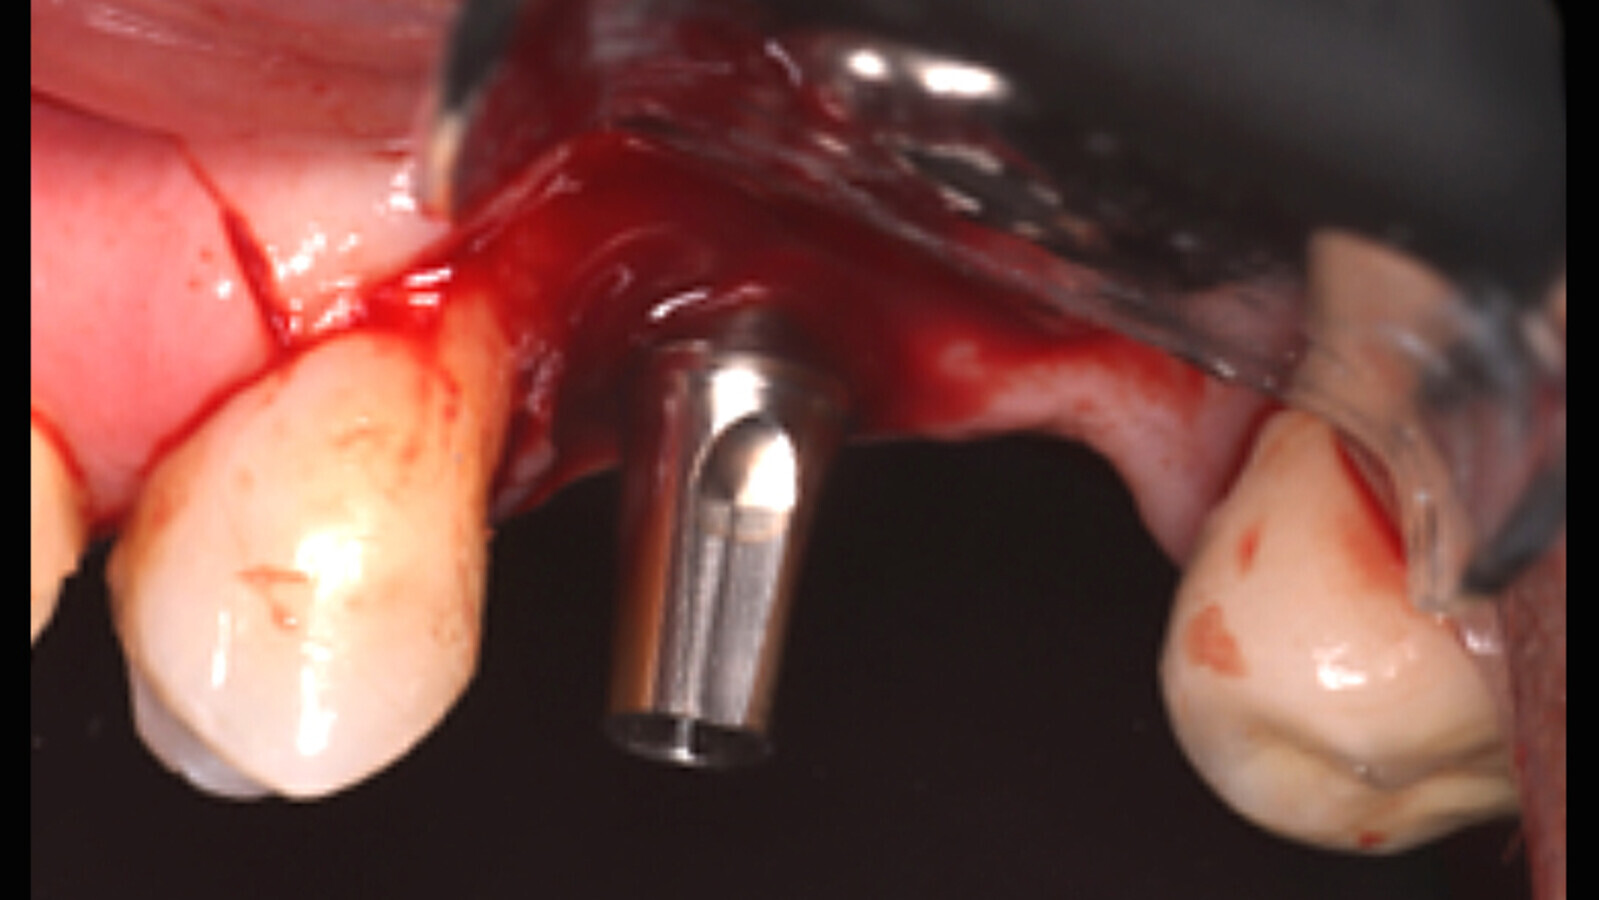

Figura 5a. Cirugía con la guía quirúrgica y colocación del implante.

Figura 5b. Cirugía con la guía quirúrgica y colocación del implante.

Figura 5c. Cirugía con la guía quirúrgica y colocación del implante.